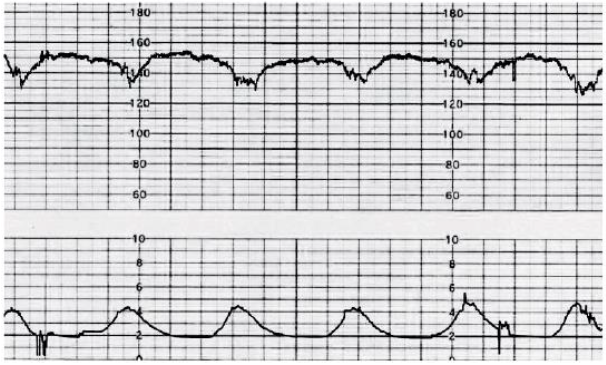

Observe a cardiotocografia abaixo.

A desaceleração presente nesta cardiotocografia é provavelmente causada por